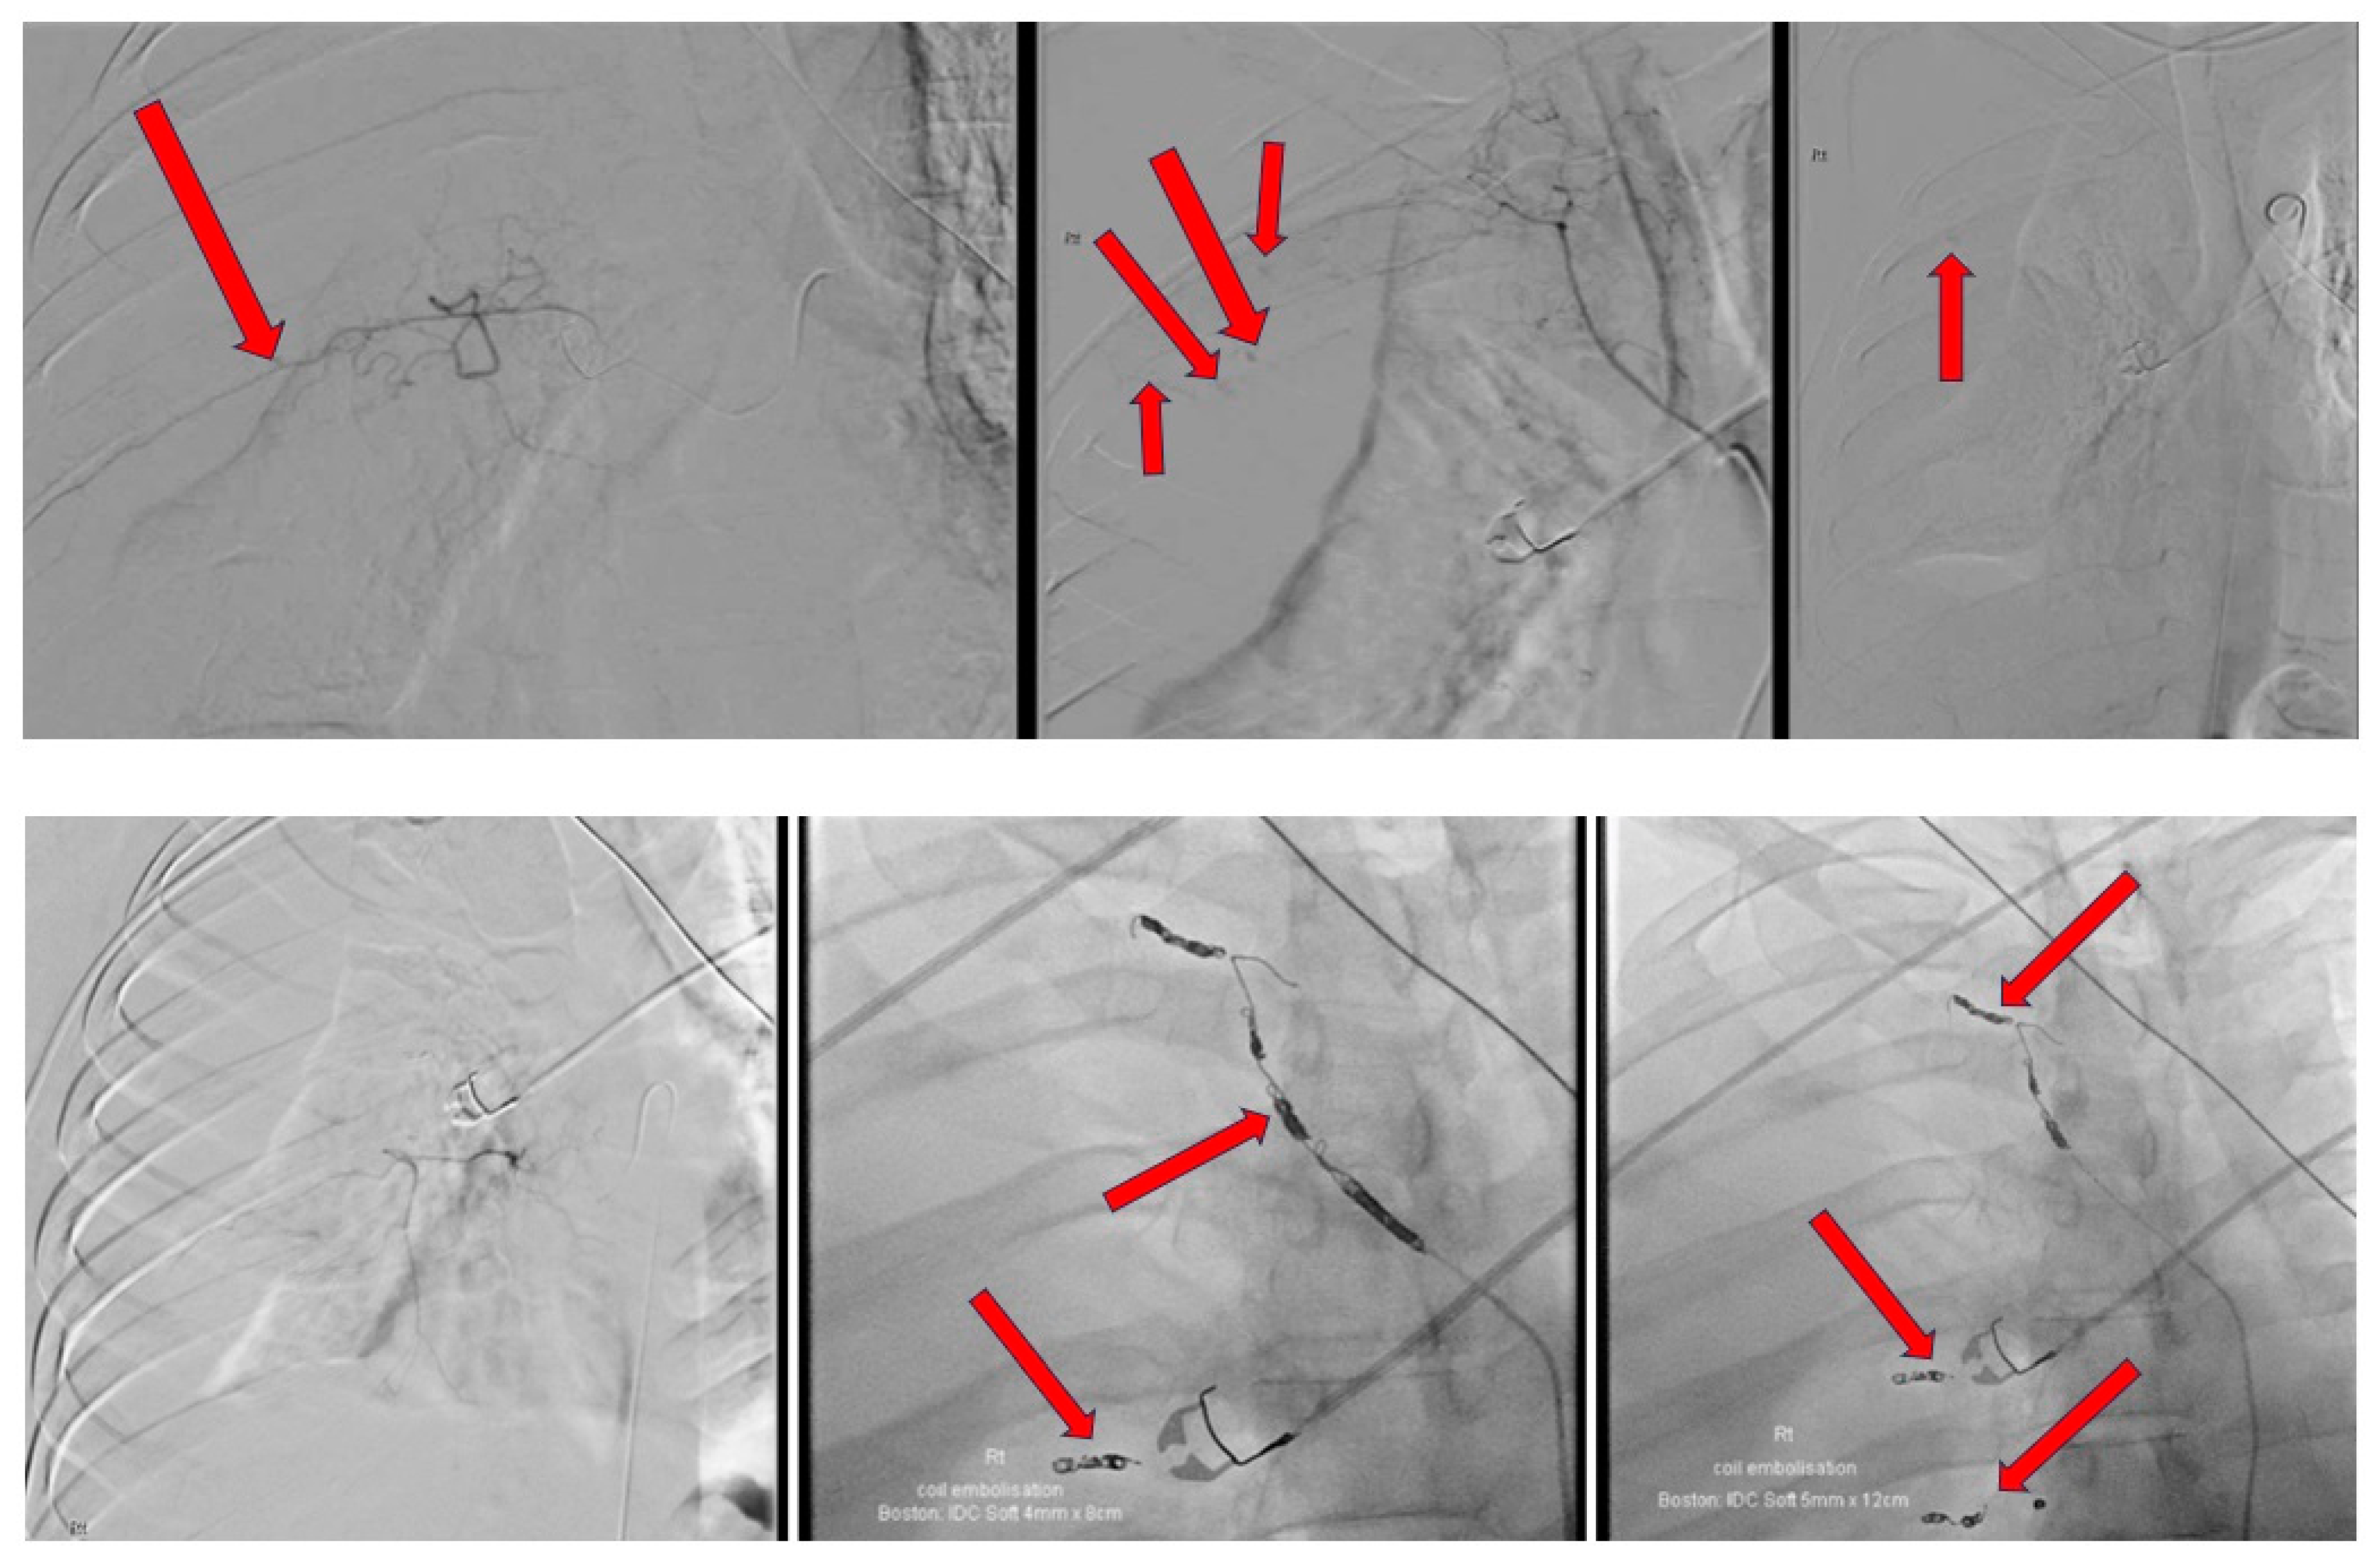

The intra-procedural description and images are provided in Figure 4. A 14-French Pigtail intercostal catheter was inserted post-procedure which drained an approximate amount of 700 mL of blood in an hour. The intercostal catheter was left in situ at a draining pressure of negative 20 mmHg. Repeat bloods showed a further significant drop in hemoglobin, from 135 g/dL to 95 g/dL, to 90 g/dL, to 81 g/dL, down to 78 g/dL, with a raised lactate of 3.9 mmol/L. A repeat CT angiogram was carried out to evaluate for any causes of active bleeding; the images can be found in Figure 5. As a result of no significant findings on the CT angiogram to account for the falling hemoglobin, an explorative thoracotomy was agreed upon. An extrapleural hematoma of approximately 2 L of blood was found in the extrapleural space. No active bleeding source was found. There was a collapsed right lung sparing the apical and anterior segments of the upper zone. The right lung fully expanded post-drainage of the blood in the extrapleural space. He remained intubated for 5 days post-explorative thoracotomy on a noradrenaline infusion. Despite developing ventilator-associated pneumonia and being severely deconditioned secondary to these events, he recovered well over the course of a week and was discharged back to the regional hospital for further rehabilitation. CXR prior to discharge is shown in Figure 6. A concise timeline of the key sequences of events at each site is shown in Figure 7.

Figure 4. Selective angiography of the right intercostal arteries and embolization of multiple areas of active bleeding with right femoral artery approach—active bleeding from several posterior intercostal arteries with significant right hemothorax. Right hemothorax progressed in size throughout duration of procedure, associated with mediastinal displacement to the left. Contrast extravasation noted from right third and fourth intercostal arteries laterally. Right first, second, third, and fourth posterior intercostal arteries have multiple areas of active bleeding. Particle embolization was performed using Spongostan particles to right first, second, third, fourth, sixth, and seventh intercostal arteries. Multiple detachable coils (measuring 2 mm to 5 mm in diameter) deployed within the bleeding intercostal arteries proximally.